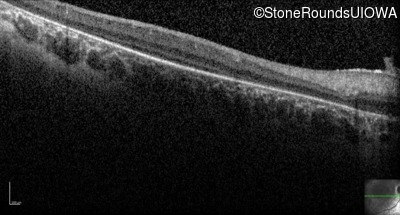

Optical Coherence Tomography - Right - Light Perception

Exemplar / OCT Stack

OCT Stack